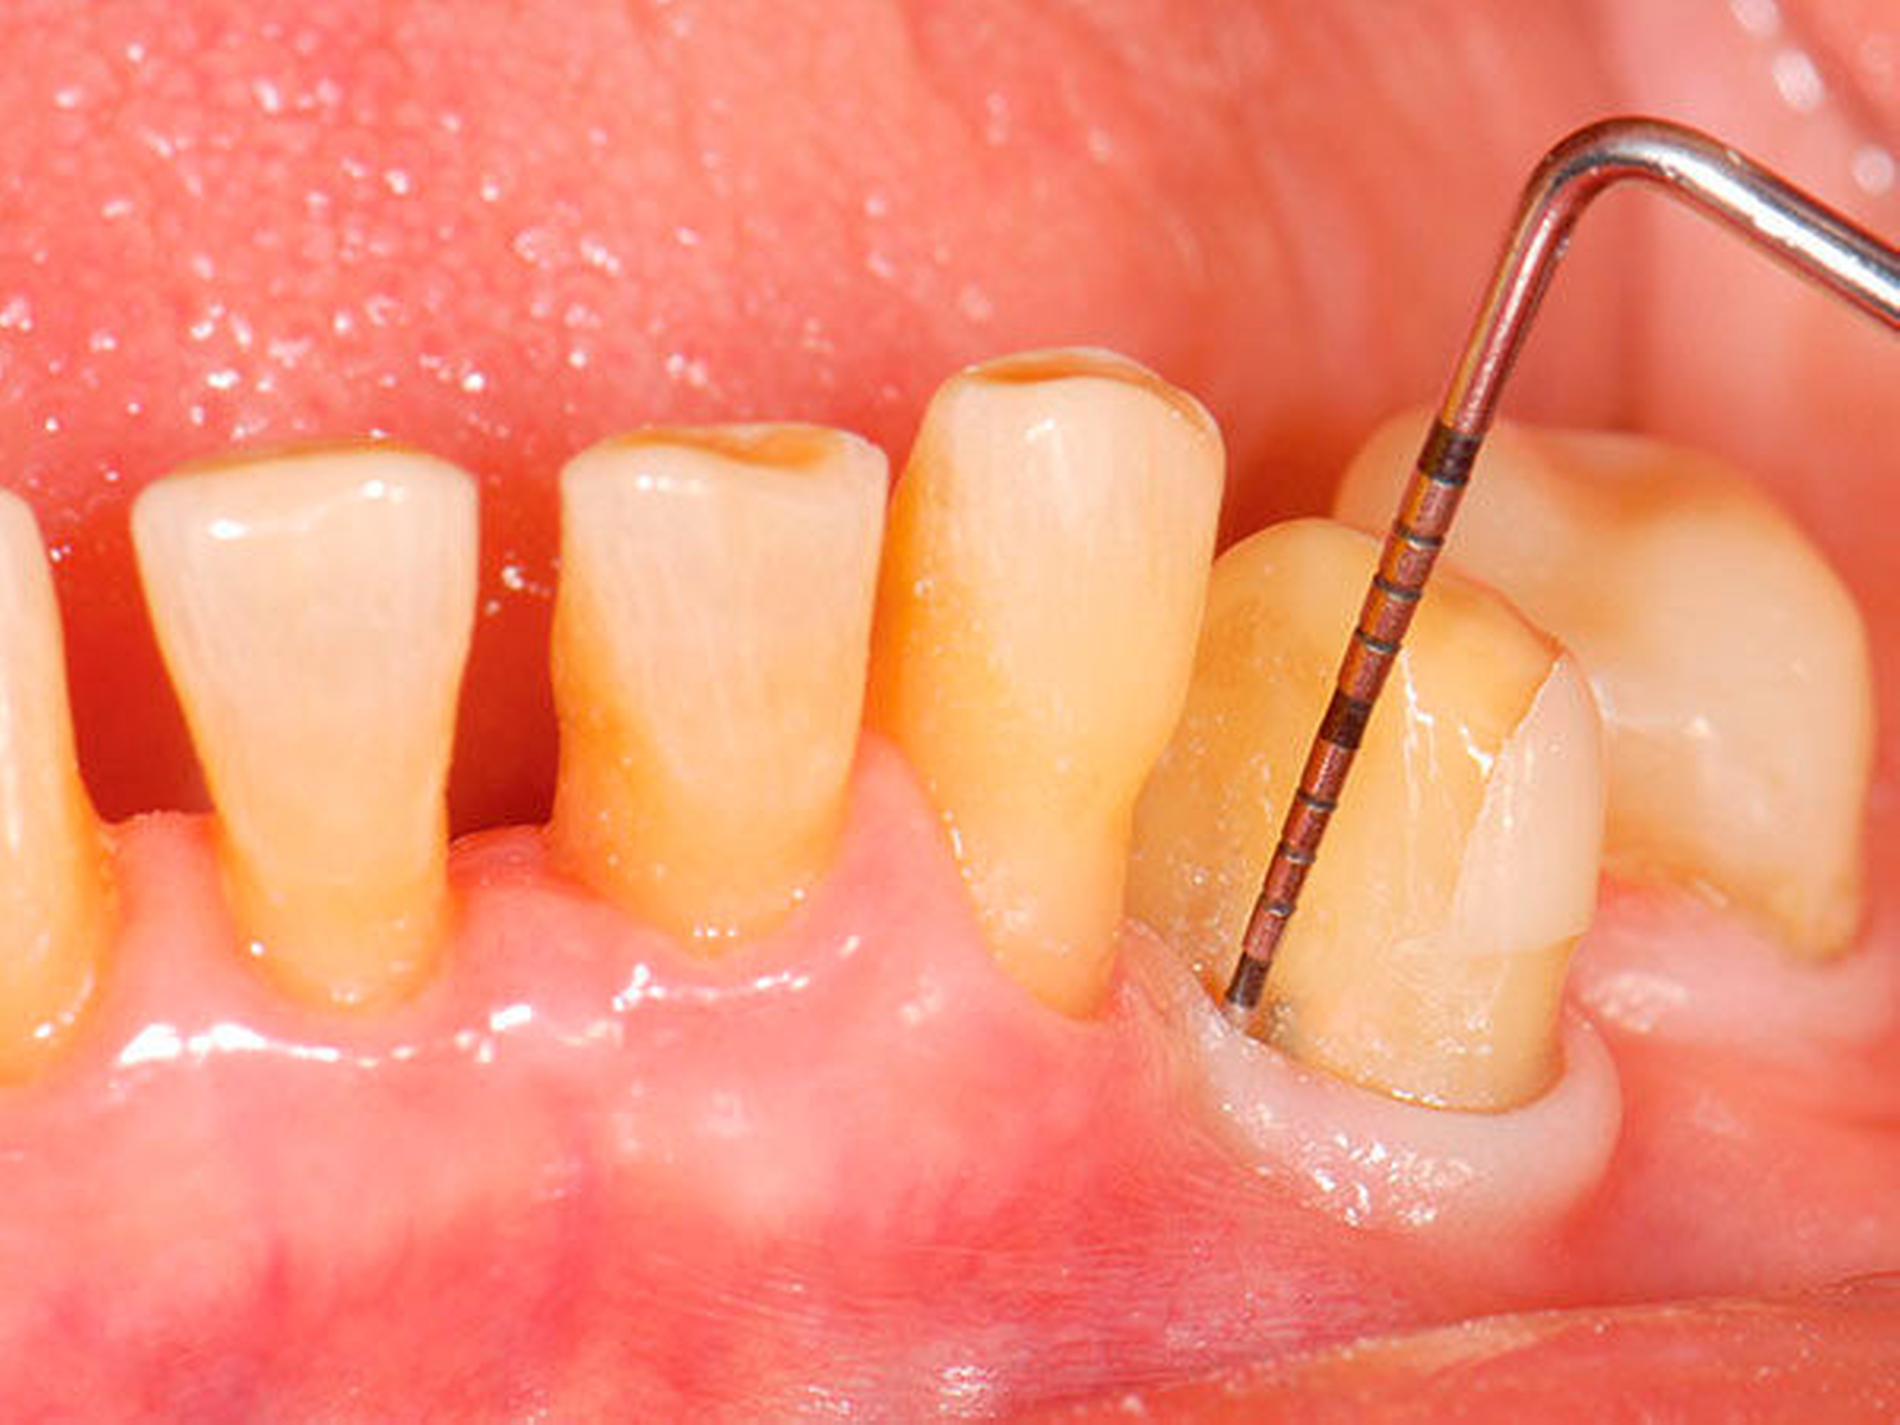

3. Restaurative Versorgungen bei Wurzelkaries

Freiliegende Wurzeloberflächen können im Alter ein locus minoris resistentiae für Karies sein. Im Zusammenspiel ungünstiger Ernährungsgewohnheiten, nachlassender Mundhygiene sowie Änderungen von Speichelquantität und -qualität kommt es zuweilen zu einem präventiv und restaurativ schwer beherrschbaren Auftreten von Wurzelkaries. Gut zugängliche Kariesläsionen können mit einphasig eingebrachtem Komposit (R1-Restaurationen) angegangen werden (Abbildungen 3 bis 5). Bei schwerer zugänglichen Arealen kommt ein zweiphasiges Vorgehen in Betracht (R2-Restaurationen). Das Vorgehen bei der R1- und bei der R2-Technik wurde mehrfach beschrieben [Frese et al., 2014a, b, c, d; Staehle et al., 2014, 2017]. Im Fall von zirkulärer Wurzelkaries sollte frühzeitig eingegriffen werden, da ansonsten die gesamte Zahnkrone frakturieren kann.

Wenn irgend möglich, sollte deshalb erwogen werden, einen Erhaltungsversuch wenigstens bei den gut zugänglichen Schneide- und Eckzähnen vorzunehmen, auch wenn die Prognose unsicher ist und Rezidive der Wurzelkaries zu erwarten sind. Die in Abbildung 5 gezeigte Patientin lebte zunächst noch zu Hause und wurde von einer Pflegeperson täglich betreut. Nach Umzug in ein Pflegeheim wird sie von ihrer ehemaligen Pflegerin nach wie vor ein- bis zweimal wöchentlich aufgesucht. Die Pflegerin nimmt bei ihr ein- bis zweimal wöchentlich eine Zahnreinigung mittels Zahnbürste und Interdentalraumbürsten vor, was mit einem Zeitaufwand von jeweils maximal fünf bis zehn Minuten verbunden ist. Obwohl sich nach zwei Jahren an einigen Zähnen ein Kariesrezidiv eingestellt hat, konnte der Zahnbestand gehalten werden.